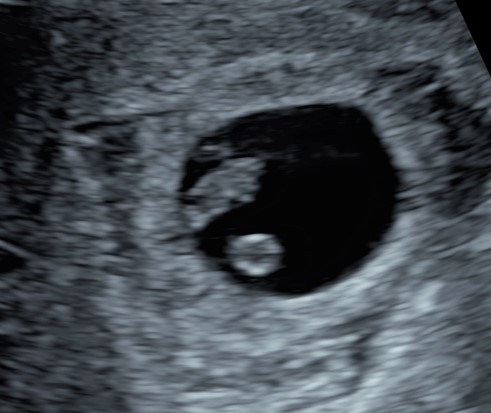

Con l’ecografia, che, a seconda dell’epoca gestazionale e dalla posizione dell’utero, può essere fatta sia per via addominale che transvaginale, potremo vedere un piccolo fagiolino con al suo interno il “cuoricino” che batte, facendoci realizzare che quei pochi millimetri di vita e di amore sono l’evento più sconvolgente della propria vita, e da qui in poi niente sarà più come prima.

Tipicamente la prima ecografia va fatta dopo la 6° settimana per evitare di non vedere nulla e rimanere conseguentemente delusi.